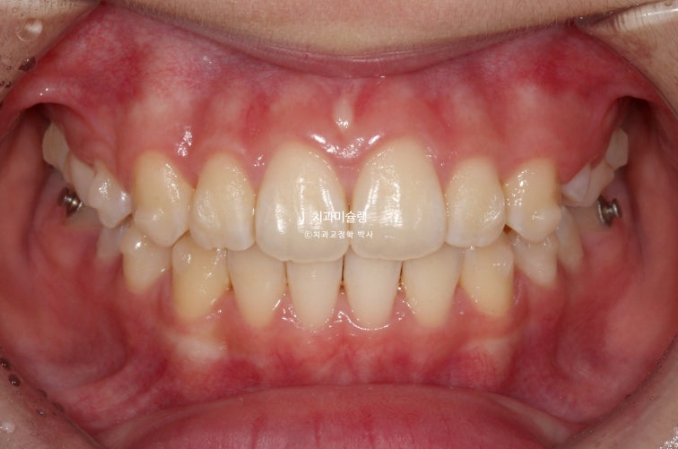

25.11

중심선은 잘 맞고 배열도 좋습니다.

그 사이 마지막 작은어금니까지 모든 영구치가 나와 교합이 완성이 되었습니다.

1급 물샐틈 없는 교합관계를 보입니다.

이제 전후 비교 보겠습니다.

총 치료기간은 1년 6개월이고 중간에 영구치 나오기를 기다리며 쉬는 시간이 7개월이고 액티브하게 장치를 열심히 끼던 시간이 약 11개월입니다

재제작은 총 1회 했습니다.